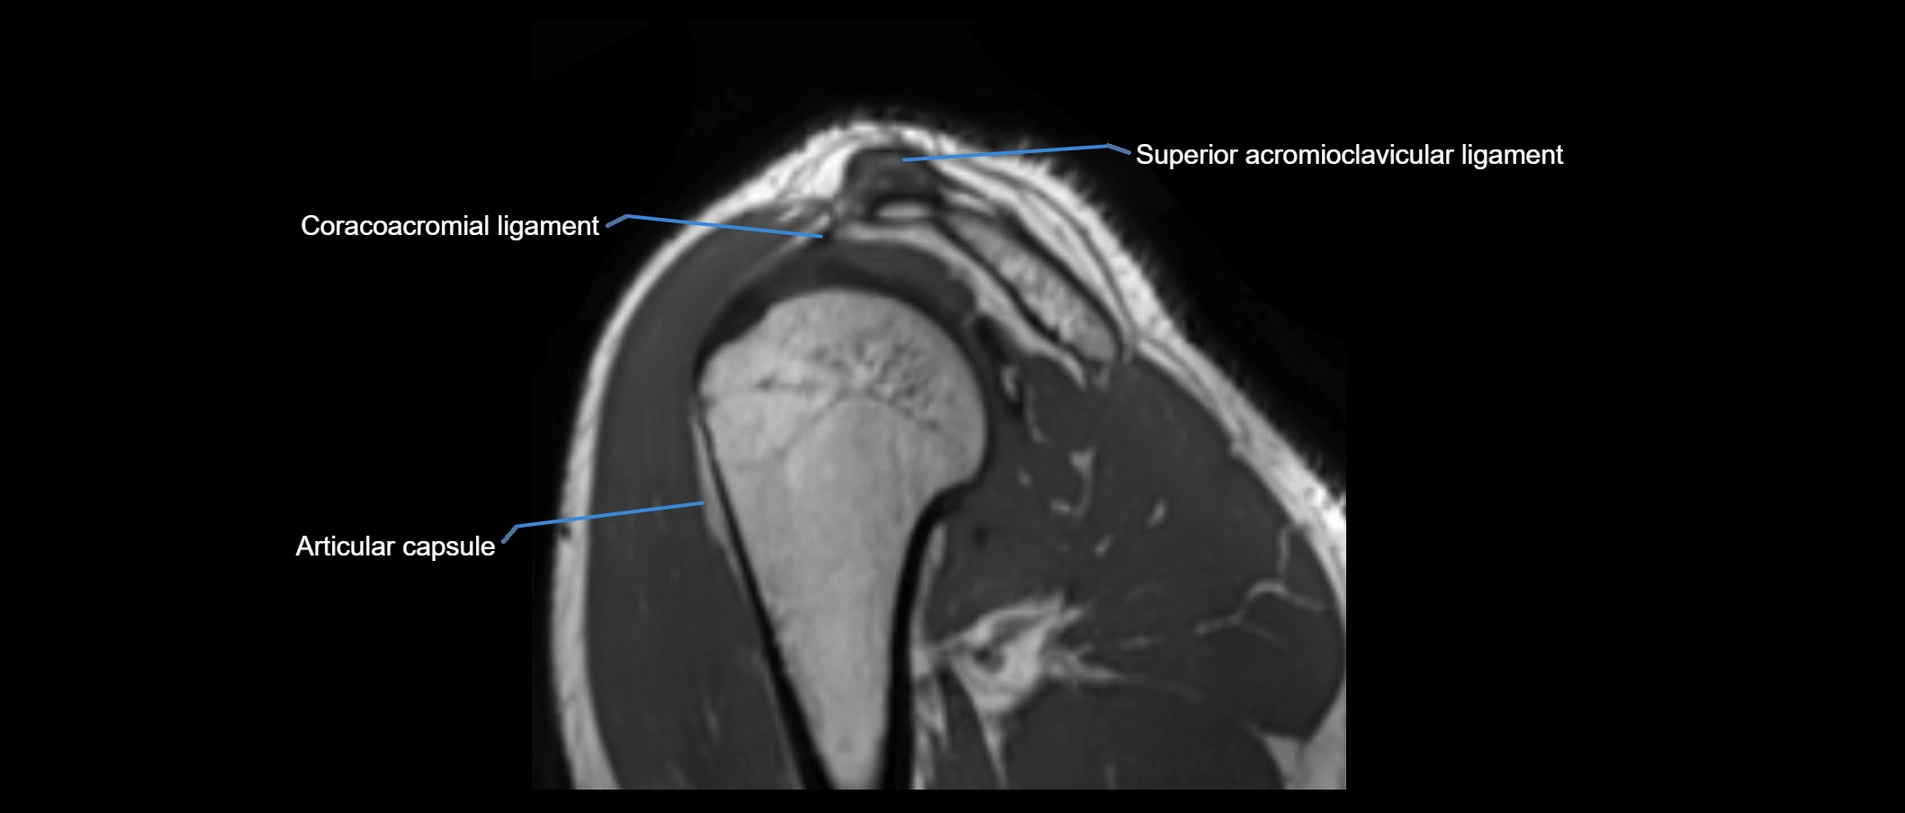

CT image

image